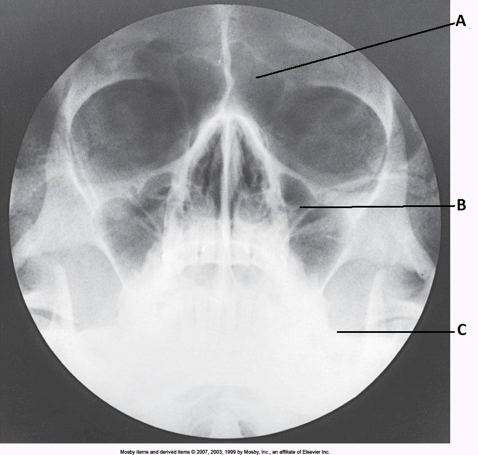

____ 10. Examine the image of the paranasal sinuses below. The letter D labels the:

a. crista galli

b. vomer

c. cribriform plate

d. perpendicular plate of the ethmoid bone

bb. vomer

____ 11. Examine the image of the paranasal sinuses below. What projection (method) is demonstrated?

a. PA axial (Caldwell)

b. parietoacanthial (Waters)

c. SMV

d. lateral

b

____ 168. What projection (method) of the facial bones is demonstrated in the image below?

a. AP axial (Towne)

b. PA axial (Caldwell)

c. parietoacanthial (modified Waters)

d. parietoacanthial (Waters)

delete

cc. parietoacanthial (modified Waters)